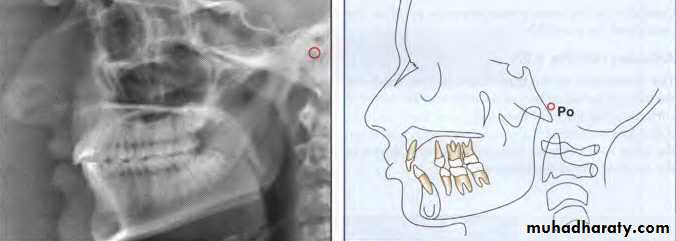

Porion (Po)

The "top" of the external auditory meatus. Sometimes,because porion is quite unreliable, the "top" of the shadow of the ear rods is used, which is known as

“machine porion".